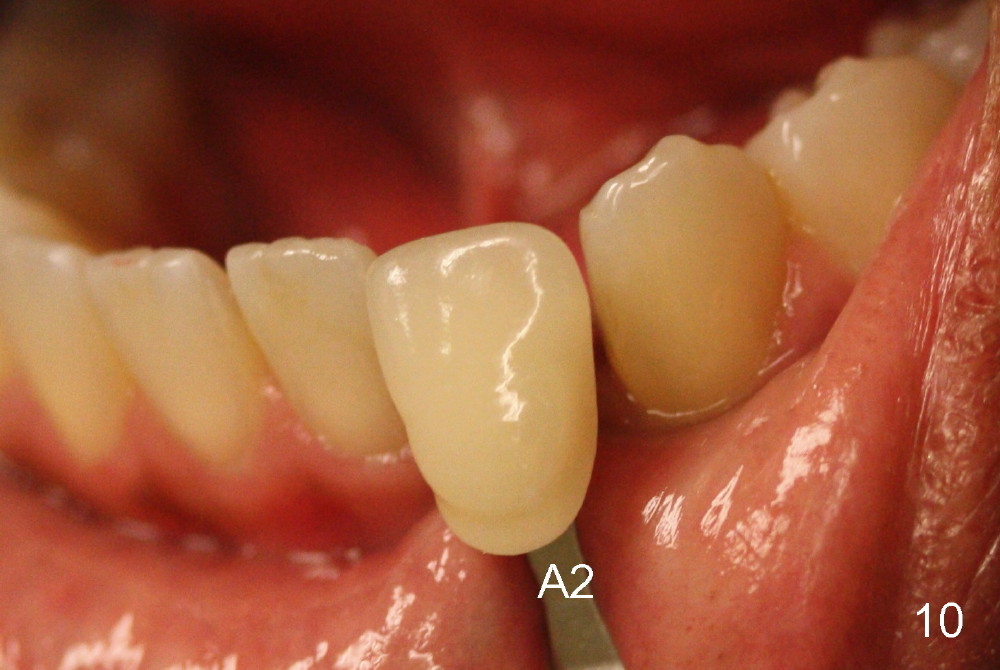

Fig.10: A2 shade guide.  The patient requests A1 for the incisal edge and body and A2.5 for the cervical region.  Fig.11 is taken 22 months post 2nd cementation (4 years postop).  The implant crown remains normal 1 year 10 months post 2nd cementation (4 years 10 months postop, Fig.12,13).